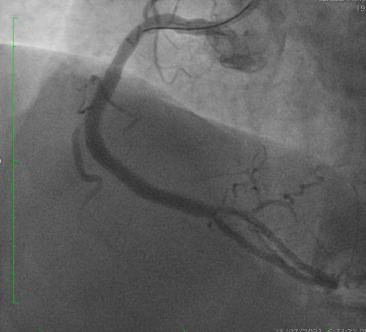

PCI was performed via single radial access with a 6F short-tip AL guiding catheter and Finecross microcatheter. 3D wiring with UB3 under orthogonal views; escalation to Gaia 3. Anchor ballooning in the RV branch improved support. The wire successfully crossed into the PLV. Predilation with a small balloon, followed by scoring ballooning. A Crusade dual-lumen catheter enabled Gaia 3 wiring into the PDA, which was predilated with a 2.5 mm balloon. IVUS revealed undersized and extensively malapposed stents contributing to ISR and prior very late thrombosis. High-pressure NC 3.75 mm ballooning improved expansion, though full correction was limited by the original stent size. A hybrid treatment strategy was chosen—DCB for both PLV and PDA (3.0¡¿20 mm and 3.0¡¿15 mm respectively, with DCB-assisted kissing), and DES reconstruction of the mid-to-proximal RCA using 4.0¡¿38 mm and 4.0¡¿20 mm stents delivered with guide extension support. Final IVUS confirmed optimal expansion and apposition without edge dissection. Final angiography showed TIMI 3 flow with no complications. At 9 months, angiography demonstrated patent RCA stents and positive remodeling at the PLV ostium.